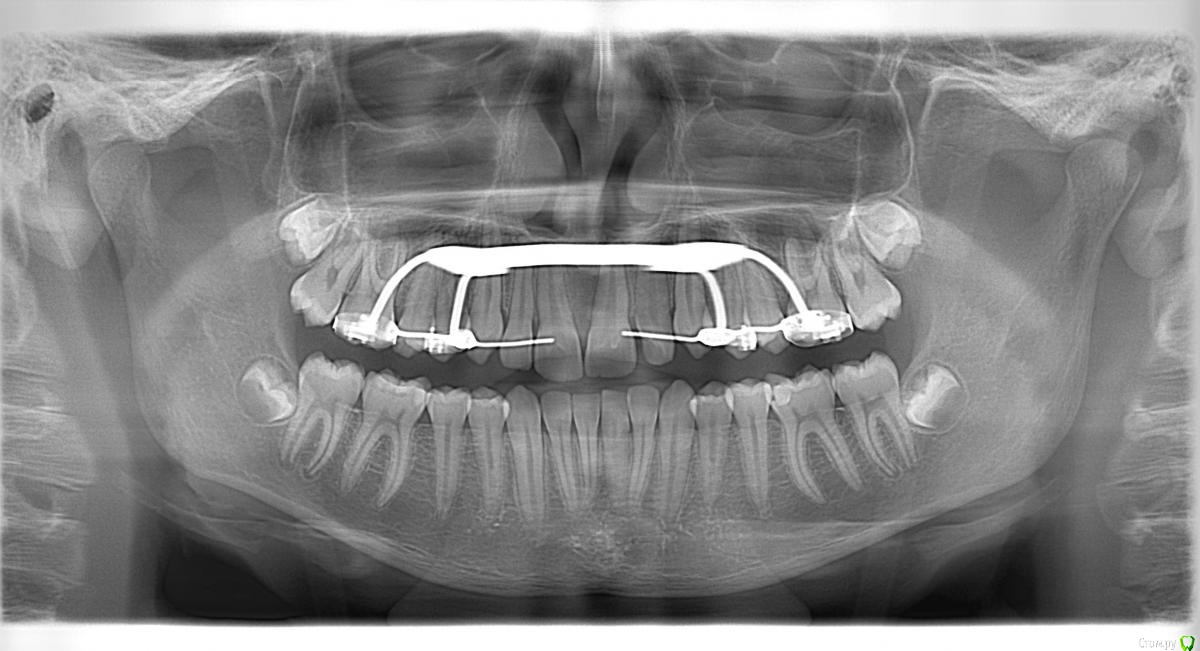

natkoorth1991 Опубликовано 28 августа, 2015 Поделиться Опубликовано 28 августа, 2015 мальчик, 13 лет, премоляры удалять не хотели, поставила хайракс на в / ч- получила перекрестную окклюзию. Извините за плохие фото( Что теперь делать? фото после: Ссылка на комментарий

Molox Опубликовано 29 августа, 2015 Поделиться Опубликовано 29 августа, 2015 Выведете. Наверх поставьте зауженную дугу, на низ - стандартную или широкую. Поскольку диастемы не появилось, у меня стойкое подозрение, что расширение было зубоальвеолярным, значит на брекетах вернуть все можно. Скажите, а зачем вообще аппарат ставили? Дефицит места минимальный, десна хорошая; на брекетах за 6 мес все бы расправилось. Ссылка на комментарий

Yana guapa Опубликовано 29 августа, 2015 Поделиться Опубликовано 29 августа, 2015 конечно, показаний для PRE здесь не было. но раз уж поставили, то поставили.Я бы теперь скручила винт в обратную сторону. будет нужный результат. Потом сняла бы аппарат и просто сделала бы перерыв. Премоляры сами немного вернуться к исходному положению Нет ТРГ. Но стакой инклинацией верхних центральных резцов могу предположить, что НЧ смещена кзади. Если это выяснится, и в ходе лечения НЧ будем перемещать вперед, то это тоже поспособствует лучшему смыканию. ждем снимков 2 1 Ссылка на комментарий

Maverick Опубликовано 29 августа, 2015 Поделиться Опубликовано 29 августа, 2015 Хайрекс был не по показаниям. Обычная брекет система с этим справилась бы прекрасно. Снимайте его. Пока костная мазоль не образовалась переживать не надо, а это обычно занимает 4-5 месяцев, сняв аппарат получите рецидив и все вернется на круги своя. Либо как предложили выше скручивайте назад такими же темпами. Брекеты не ставьте пока не получить изначальную форму дуги, ну или близкую к ней. Трг это конечно хорошо, но надо смотреть на профиль - это показатель лечения, слепо доверять цифрам не совсем хорошая идея. Лечим не цифры, а людей. 2 1 Ссылка на комментарий

Maverick Опубликовано 29 августа, 2015 Поделиться Опубликовано 29 августа, 2015 Выведете. Наверх поставьте зауженную дугу, на низ - стандартную или широкую. Поскольку диастемы не появилось, у меня стойкое подозрение, что расширение было зубоальвеолярным, значит на брекетах вернуть все можно. Скажите, а зачем вообще аппарат ставили? Дефицит места минимальный, десна хорошая; на брекетах за 6 мес все бы расправилось. Диастема может не появляться. Все зависит от интенсивности раскручивания винта. При медленном, а не агрессивном расширении не бывает диастемы в области центральных резцов. Ссылка на комментарий